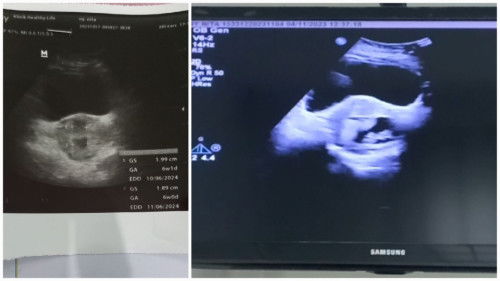

Bunda, mau tanya².. Ini foto USG 1 waktu baru tahu hamil, indikasi 2 kantung hamil (dokter 1) Foto USG 2 baru tadi diambilnya terkonfirmasi janinnya 1 😇(dokter 2) Tadi saya periksa ke obgyn bund, bulan kemarin saya periksa ke bidan sama ke dokter yg faskes. Nah disini bunda² ada yg double periksa kaya saya ke bidan sama ke obgyn jga kah ? Utk obat dan vitaminnya yg di minum hanya dari obgyn saja kan ? Atau gmna ? Mhon sharing nyaa.. Soalnya waktu hamil anak pertama , saya hanya di bidan sajaa bund. #seriusnanya #bantusharing #ingintahu